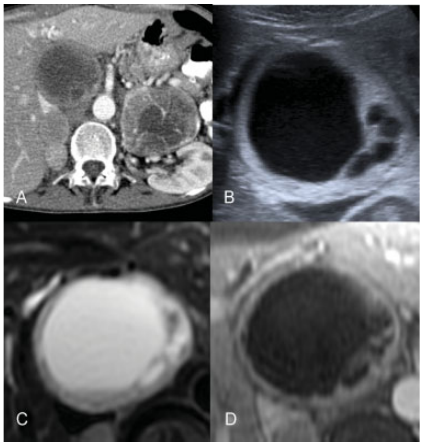

La RM es una prueba muy sensible para la detección de feocromocitoma siendo la prueba de elección para su detección debido a la ausencia de radiación ionizante. Esas lesiones se visualizan hipointensas en la secuencia potenciada en T1 y muy hiperintensas en la secuencia potenciada en T2 con zonas heterogéneas por la existencia de necrosis, hemorragia o calcificación. Tras la inyección de gadolinio realzan de manera intensa (►Fig. 9).

Feocromocitomas en paciente con MEN tipo 2. En la TC con contraste intravenoso (A) se identificaron feocromocitomas bilaterales. En la ecografía (B) se apreció feocromocitoma derecho ampliado con zonas quísticas y capsula gruesa. En la RM se identificó la misma lesión que en ecografía, lesión encapsulada y heterogénea que depende de glándula suprarrenal derecha que en la secuencia potenciada en T2 (C) presentó un aspecto heterogéneo objetivándose marcadamente hiperintensa, y con captación de predominio periférico en la secuencia con gadolinio (D).